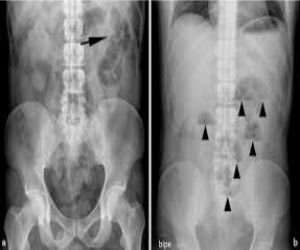

Radiografia de abdomen.

Es un examen imagenológico para observar órganos y estructuras en el abdomen. Los órganos incluyen

- El bazo.

- El estómago.

- Los intestinos.

Cuando este examen se hace para observar las estructuras de la vejiga y el riñón, se denomina radiografía de RUV (riñones, uréteres y vejiga).